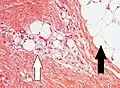

Histopathology of liposarcoma, H&E stain, with the main features:[5]

- Spindle cells with enlarged, hyperchromatic nuclei.

- Apparently univacuolated adipocytes (may look normal).

- Lipoblasts (multivacuolated), but neither necessary nor sufficient for diagnosis of liposarcoma. -